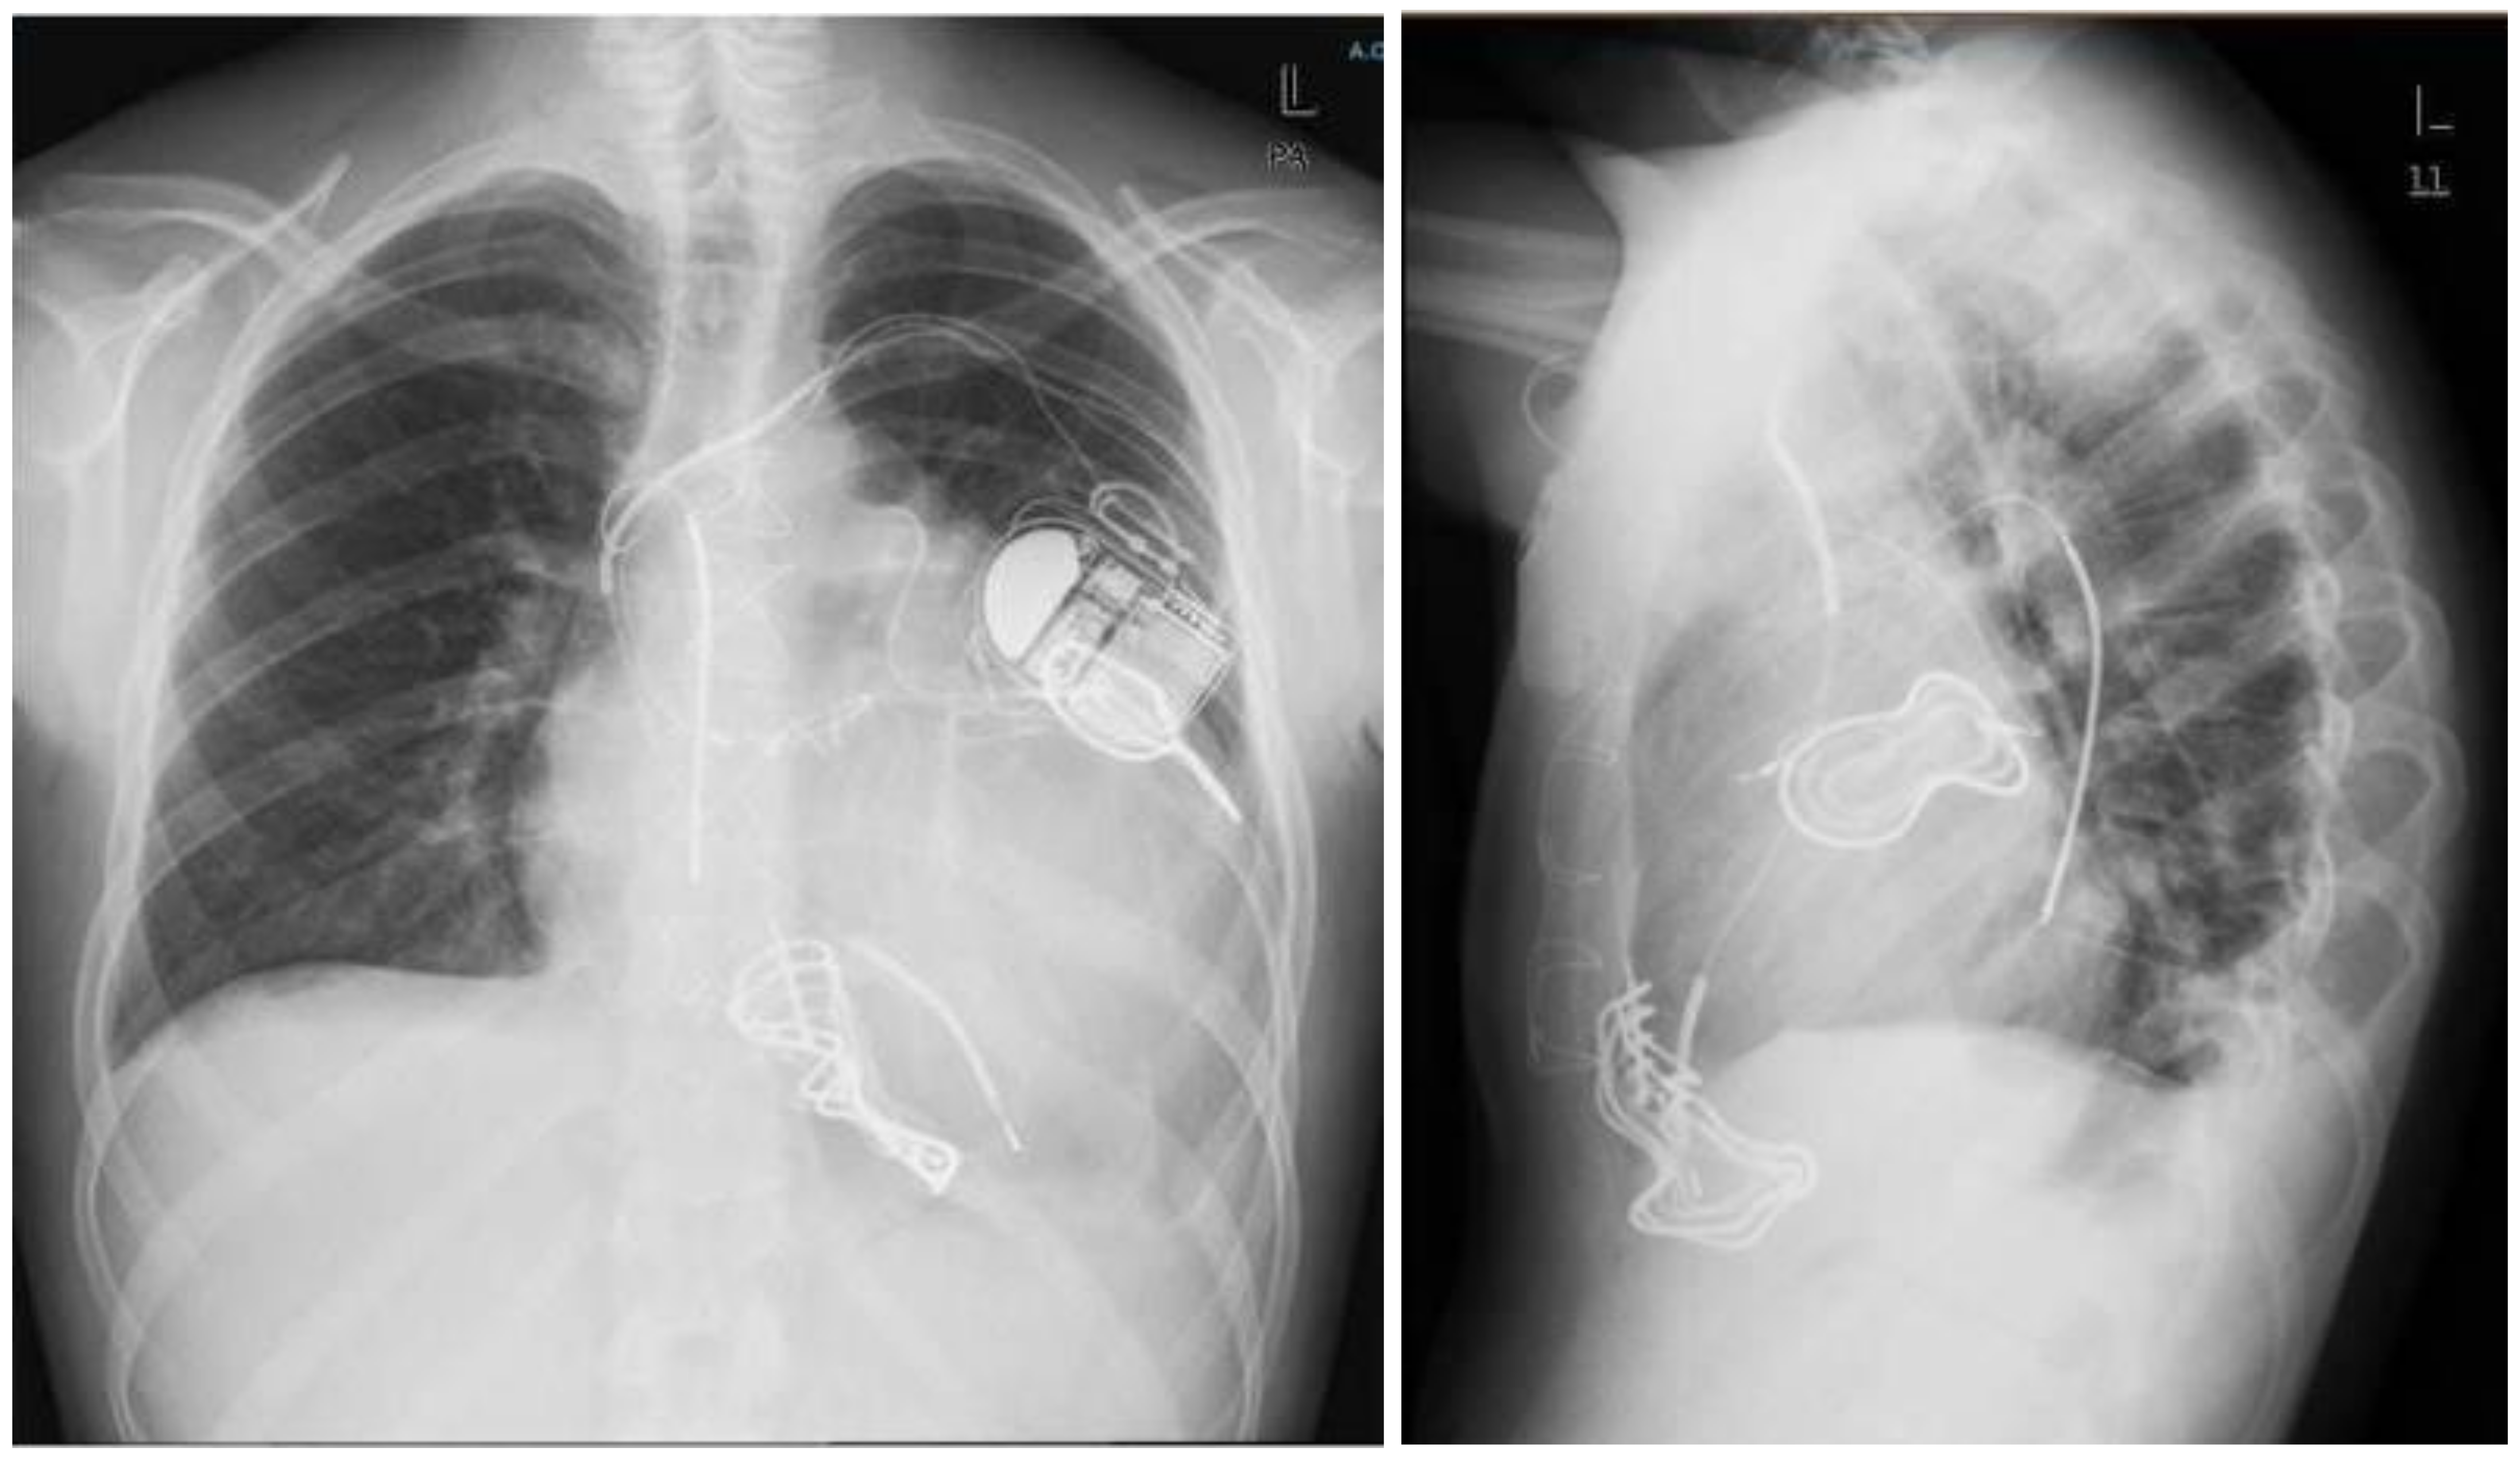

The patient underwent the implant of a new trans-venous defibrillation coil lead (Medtronic, Inc. ST Anthony, MN) in the azygos vein (Figure 3). In order to maximize the defibrillation success, a new ICD (Inventra 7 VR-T, Biotronik, Inc., Lake Oswego, OR, USA) was implanted with a high nominal energy of 45 J (40.5 J delivered) from the first shock. After this implant, the connection of the high energy included the distal coil of the first endocardial lead and the new coil in azygos.

Figure 3.

Lateral (left panel) and AP (right panel) chest X-ray after azygous vein ICD lead implantation. The shock pathway was formed by the old endocardial distal coil; the new floating coil was placed in the azygos vein and the can.

ICD was programmed with a VF zone above 200 bpm and a therapy including eight shocks at 45 J, automatic alternating polarity and a Bifasic-2 wave form. The shock pathway was formed by the old endocardial distal coil; the new floating coil was placed in the azygos vein and the can.